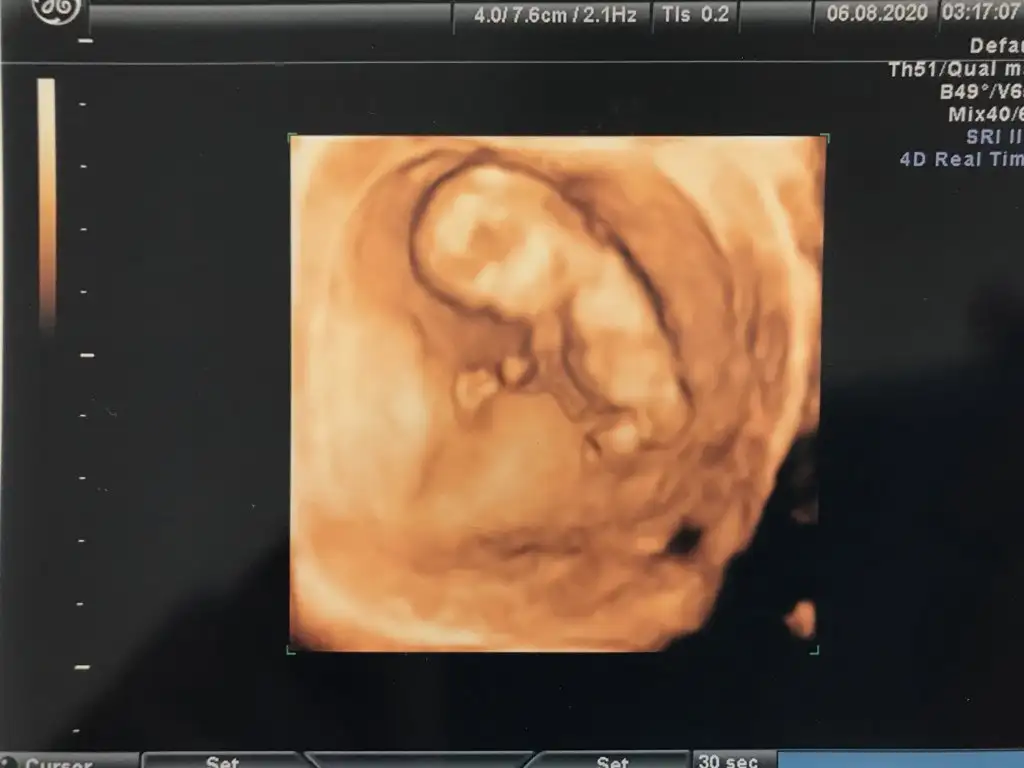

Erkek gibi başka usgde paylaşın teyit edeyim 11 12 13 haftalar olmalı USG kaç haftalıkTahmin varmi kızlar Eki Görüntüle 2671896

12+2 cnmErkek gibi başka usgde paylaşın teyit edeyim 11 12 13 haftalar olmalı USG kaç haftalık